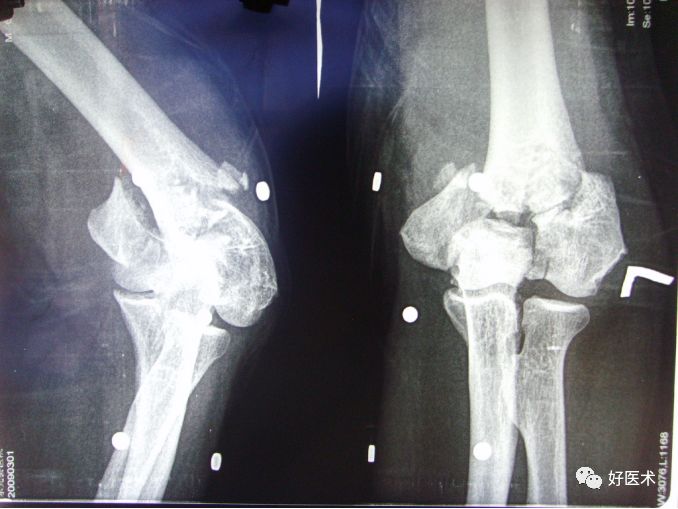

肘外翻:任何原因引起的肘外翻畸形,使尺神经张力增大,于肘关节活动过程中受到牵拉和摩擦,神经鞘逐渐增厚而导致神经受到卡压。

https__3A__2F__2Fmmbiz___qpic___cn__2Fmmbiz_png__2F3pLQOk2IRXibkcibg3gdUuSicmiceSrIstDYxnZZC1RBdg9SqgoA9gBZZvUmIeEhETrsiahgT0UfhMwibX1pepLKCFKg__2F640__3Fwx_fmt__3Djpeg__26tp__3Dwxpic__26wxfrom__3D5__26wx_lazy__3D1__26wx_co__3D1&r=https__3A__2F__2Fmp___we

其他:陈旧性骨折造成血肿机化、骨块移位、增生、囊肿、肿瘤等均可造成尺神经受压。